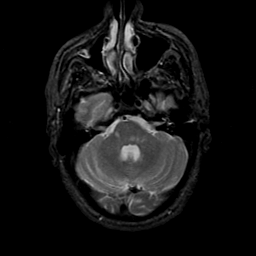

MR Study #21, November 3, 1991 -- Slice #12